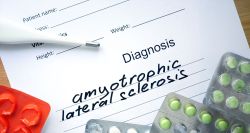

ALS: A Protein Signature that Could Change the Game

Bélinda Ibrahim 26/11 10:30 - Reading : 3 minute(s)

ALS Charcot’s Disease Science USA Blood Test

In the field of neurodegenerative diseases, scientists have spent decades chasing the same goal: finding an early and reliable biomarker that can reveal what the body has not yet shown. For ALS, that search has long seemed out of reach. The disease arrives quietly, progresses unnoticed, and only becomes visible once the first motor neurons are ...